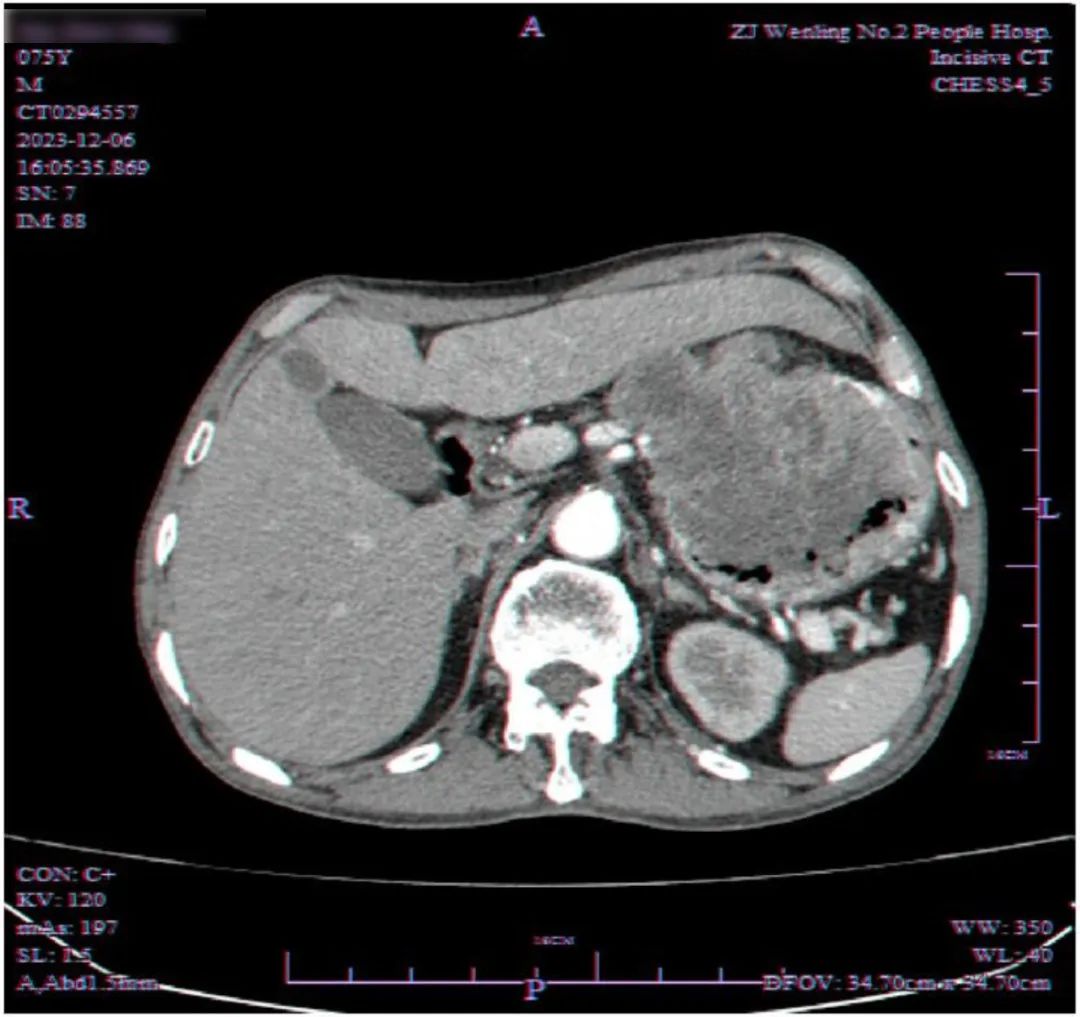

经过详细的 CT 检查,医生发现赵阿公的肝胃间隙有一个巨大的占位性病变,侵犯了胃壁并向腔内生长。这是一个极为不利的信号,意味着赵阿公的病情可能相当严重。

这场手术历时整整一天,从上午 9 点一直进行到下午 4 点。手术涉及胃肠外科、胸外科等多个团队,肿瘤侵犯了食管、胃、肝、膈肌以及心包多个部位,最终在团队的默契配合下成功切除了肿瘤,肿瘤近似麒麟瓜大小,重量近 4 斤!